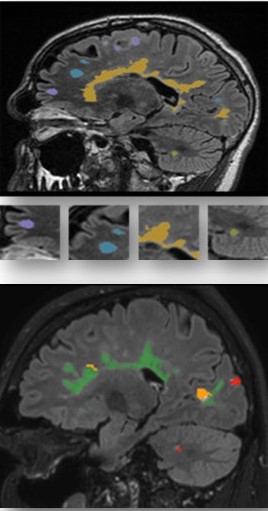

Lo studio mette insieme tre tipi di informazioni: i dati che arrivano dalla pratica clinica quotidiana, quelli raccolti in studi osservazionali e i risultati dei trial clinici. Il database, avviato lo scorso anno, sta crescendo rapidamente. Oggi include più di 55.000 risonanze magnetiche provenienti da oltre 7.500 persone con sclerosi multipla, accompagnate dai relativi dati clinici disponibili. Tutte le immagini MRI sono state analizzate in modo quantitativo dalla società icometrix, con sede in Belgio. Grazie a questa ricchezza di dati — che include anamnesi, terapie, ricadute, esami radiologici, imaging retinico (OCT), potenziali evocati e altri biomarcatori — sarà possibile sviluppare modelli AI in grado di prevedere con maggiore precisione l’evoluzione della malattia in ciascun paziente, individuare le terapie più efficaci e distinguere peggioramenti legati a ricadute infiammatorie da progressioni silenti.

Wim Van Hecke, CEO di icometrix, ha aggiunto: «La risonanza magnetica è fondamentale per monitorare la progressione silente della sclerosi multipla. Il progetto CLAIMS farà avanzare il settore grazie alla misurazione sia dei processi infiammatori sia della patologia “subdola” e persistente. Questo approccio innovativo è decisivo per consentire valutazioni guidate dai dati, offrendo ai pazienti le migliori possibilità di preservare la qualità di vita».